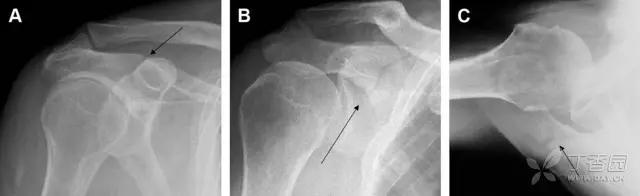

28 骨折伴盂肱关节不稳

肩关节是最容易脱位的关节之一,肩关节脱位常伴随其它结构的损伤,如血管神经损伤、肩袖损伤、盂唇损伤、Bankart 损伤等。脱位本身诊断往往是明确的,容易被忽略的是其继发的伴随损伤。

需要仔细评估肱骨头、大结节、关节盂边缘、肩峰、喙突等结构。典型的 X 线投射角度包括:内旋位前后位片、外旋位前后位片(Grashey 位)、侧位(肩胛骨 Y 位)、腋位片以及改良腋位片。

图 6 肩关节前脱位伴有 Hill–Sachs 和 Bankart 损伤:(A~C)肱骨头后外侧撞击骨折,白色箭头所示为骨折的内侧边界;(A)内旋位前后位片,(B)「V」形压缩骨折的下边界(虚线短箭头),(C)Garth 位(轴向投影)示 Hill–Sachs 损伤(虚线和实线折箭头),特别是对骨性 Bankart 损伤的诊断有帮助。(D、E)MRI 进一步证实了损伤

图 7 肩关节后脱位伴有反 Hill–Sachs 损伤。(A)外旋位前后位片可见一硬化带(黑箭头),此「凹槽征」与肱骨头关节面平行;(B)腋位片进一步证实了骨折的存在